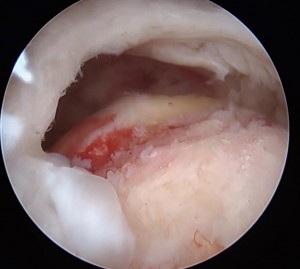

腱板が剥がれ穴があいています。下に見えるのは骨です。

2 骨にアンカー(糸のついたビスのようなもの)をうち腱板に糸を通しているところ

3 腱板に通した糸を骨に固定して終了です。

図7 損傷部の確認 関節窩から関節唇が剥がれ落ちている。

図8 損傷部の修復後の様子